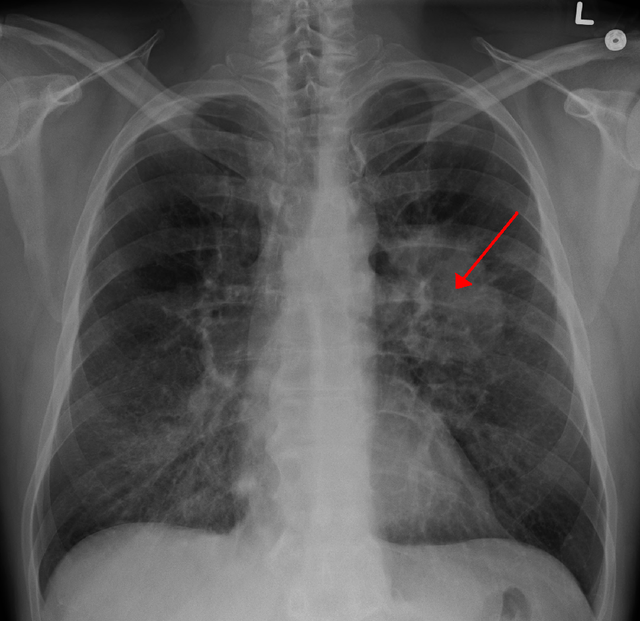

| Tranh thủ kỳ nghỉ đông, Lý Thiến Sơn đến bệnh viện địa phương khám. Kết quả ban đầu không mấy khả quan nên bác sĩ chỉ định thực hiện thêm nhiều xét nghiệm khác. Kết quả cho thấy, Lý Thiến Sơn mắc ung thư phổi. (Ảnh minh họa) |